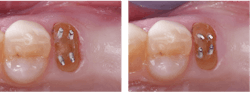

Teeth requiring significant buildup of the coronal portions can be rebuilt to near-optimum characteristics, but as is observed in dental laboratories, often dentists do not build them back to normal tooth anatomy, increasing the possibility that crowns will come off due to lack of retention.

- When one-half or more of the coronal tooth structure is gone, increase the remaining tooth strength by building it up with strongly secured composite resin to allow for the prep anatomy described above.

- Use retentive pins when necessary for retention of the buildup material. Place each pin at least 15 degrees from the long axis of the tooth (examples of titanium pins: Stabilok Dentin Pins or Filpin Pins (figure 3).